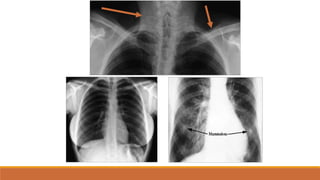

TRÀN KHÍ MÀNG PHỔI

• PHIM ĐỨNG:

• VÙNG SÁNG VÔ MẠCH NẰM NGOÀI LÁ TẠNG

• ĐƯỜNG MỜ CỦA LÁ TẠNG BAO BỌC NHU MÔ PHỔI XẸP

• TKMP ÁP LỰC: ĐẨY TRUNG THẤT VỀ ĐỐI BÊN, XẸP PHỔI THỤ ĐỘNG,VÒM

HOÀNH DẸT, RỘNG KHOẢNG LIÊN SƯỜN

• PHIM NẰM:

• GIỐNG PHIM ĐỨNG

• DH KHE SÂU

TKMP TƯ THẾ ĐỨNG

TKMP ÁP LỰC

TKMP CHỤP TƯ THẾĐỨNG

TKMP CHỤP TƯ THẾNẰM: DH khe sâu